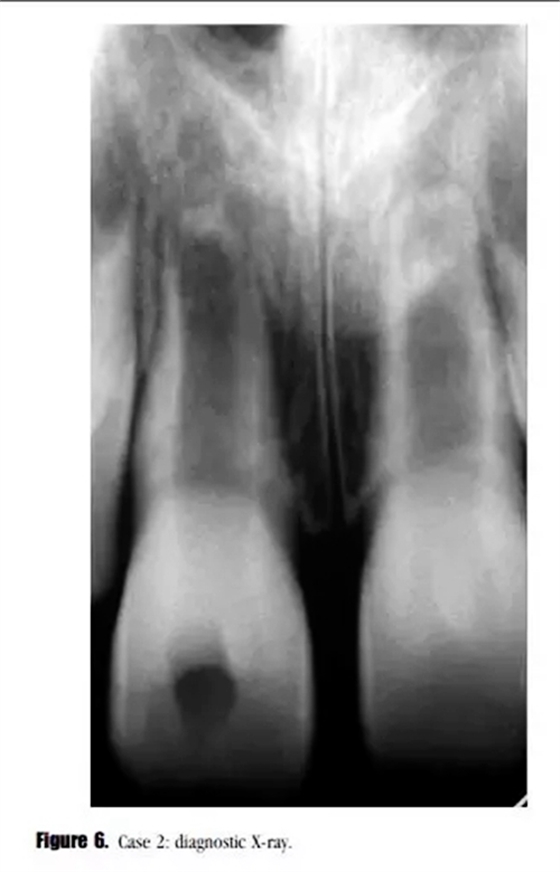

主訴:右上頜恒切牙區(qū)口腔前庭區(qū)腫脹。(圖6)。

專科檢查:牙齒輕微松動,可見開髓孔。叩診輕微不適,牙周探診深度在正常范圍內(nèi)。黏膜上可見一竇道。

輔助檢查:診斷X線示,牙根發(fā)育處于第4階段,未見明顯的根尖周透射影像,雙側(cè)中切牙根尖區(qū)可見阻射影像。21牙髓電活力測試結(jié)果正常。11診斷為:急性根尖周炎。